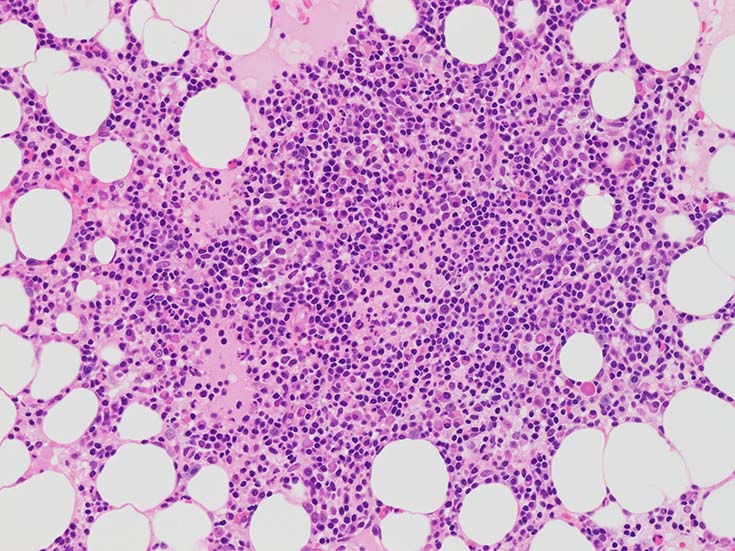

小型B細胞リンパ球, 形質細胞様リンパ球(plasmacytoid lymphocyte), 形質細胞の混在する腫瘍性増殖で骨髄, リンパ節, 脾臓病変を認める.

LPLの症例--病理所見

症例 IWTcase. 71yo male.

濾胞性・間質性膀胱炎で診療中, 検査で貧血, 血小板減少, 高γグロブリン血症(IgM Mタンパク)を指摘され, 血液内科を紹介受診となった.

Hb11.5g/dl, RBC 321x104;, MCV 104, MCHC 34.4, WBC 5200, st. 2.0, seg 79.0, Eo 0.0, Ba 0.0 Mo 5.0, ly 13.0%,plt. 11.7x104;, 連銭形成(+). IgG 2121mg/dl, IgA 163mg/dl, IgM 3233mg/dl

免疫電気泳動でIgM-κtype Mタンパクが検出された.

Bone marrow clot sectionでは, nodularな病変形成が認められる. HEでは不明瞭であるが, Naphtol-ASD-CAE-Giemas染色では mast cellの顕著な増加が明瞭に認識される.

mast cellsは周辺部に出現することが多いようである.多発性骨髄腫の結節にはmast cell増加を認めることは経験上ない.

明瞭な結節が形成されず,造血細胞内に小さなクラスタを形成して散在する場合もある.